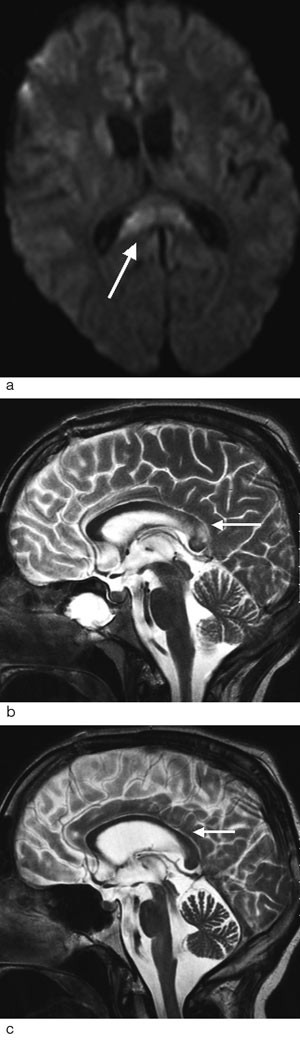

Bildediagnostikk med CT

Ved hodeskader vil CT-undersøkelse av hjernen være førstevalg siden undersøkelsen i akuttfasen er en rask og effektiv teknikk for å påvise frakturer, blødninger og ødem (25). Funn ved cerebral CT hos pasienter med skjærende skade ble først beskrevet i slutten av 1970-årene (9). Pasientene hadde alvorlig klinisk status, men CT viste likevel ikke en signifikant intrakranial blødning som kunne forklare bevisstløsheten. Typiske CT-funn ved diffus aksonal skade er små, punktformede blødninger i overgangen mellom grå og hvit substans i storhjernen og sjeldnere i corpus callosum, blod i ventrikkelsystemet og blod i subaraknoidalrommet rundt mesencephalon (fig 1) (10, 17, 20, 26). Ikke-hemoragiske lesjoner er vanskelige å påvise ved CT (25). CT vil derfor undervurdere forekomst og omfang av den diffuse aksonale skaden. Pasienter med slik skade kan ha normal CT (18). I senfasen vil CT i de mest alvorlige tilfellene kunne vise atrofi med økt ventrikkelstørrelse (9).

Diffus aksonal skade er ikke nødvendigvis diffus i sin utbredelse. Tvert imot forekommer disse lesjonene med et ganske typisk distribusjonsmønster. De fleste lesjoner er små (5 – 15 mm) og lokalisert til hvit substans og overgangen mellom grå og hvit substans i frontallappene og temporallappene (fig 2a). Ved kraftigere traumer kan det i tillegg påvises lesjoner i corpus callosum og i hjernestammen (fig 2b og c). Avhengig av hvilke strukturer som er omfattet av skaden, kan diffus aksonal skade graderes i grad 1 – 3 (tab 2) (25).